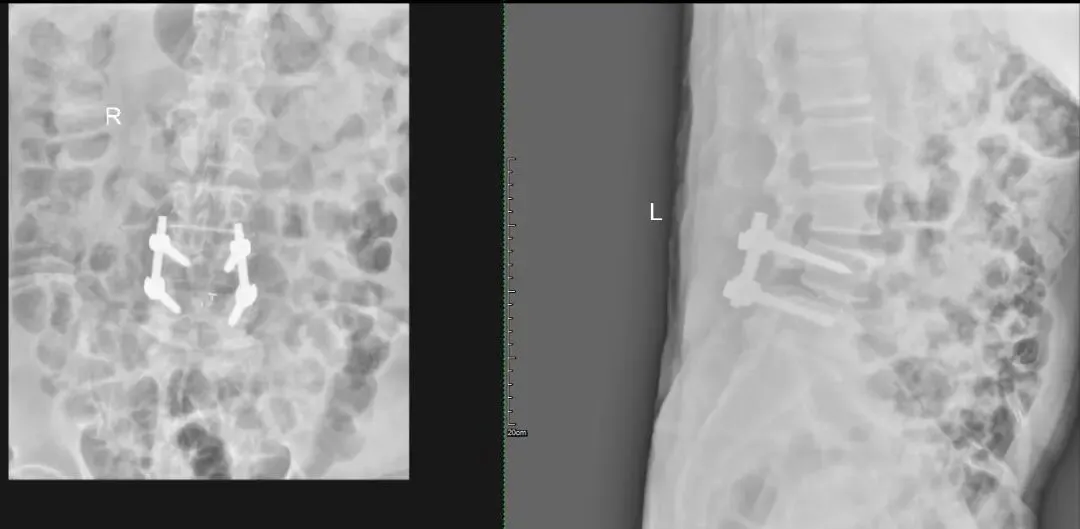

案例二:患者男,73岁,因“反复腰腿疼痛10年余,加重伴间歇性跛行2年”入院,入院诊断:1.腰椎椎管狭窄症2.腰椎滑脱3.腰椎间盘突出症。在全身麻醉下行后入路腰椎前柱融合术+腰椎间盘髓核切除伴椎板切除术+腰椎植骨术+L4/5脊髓神经根粘连松解术+2~3个椎骨融合或再融合+脊椎融合物置入术+腰椎脱位切开复位内固定术,术后恢复良好,患者及家属对治疗效果十分满意。